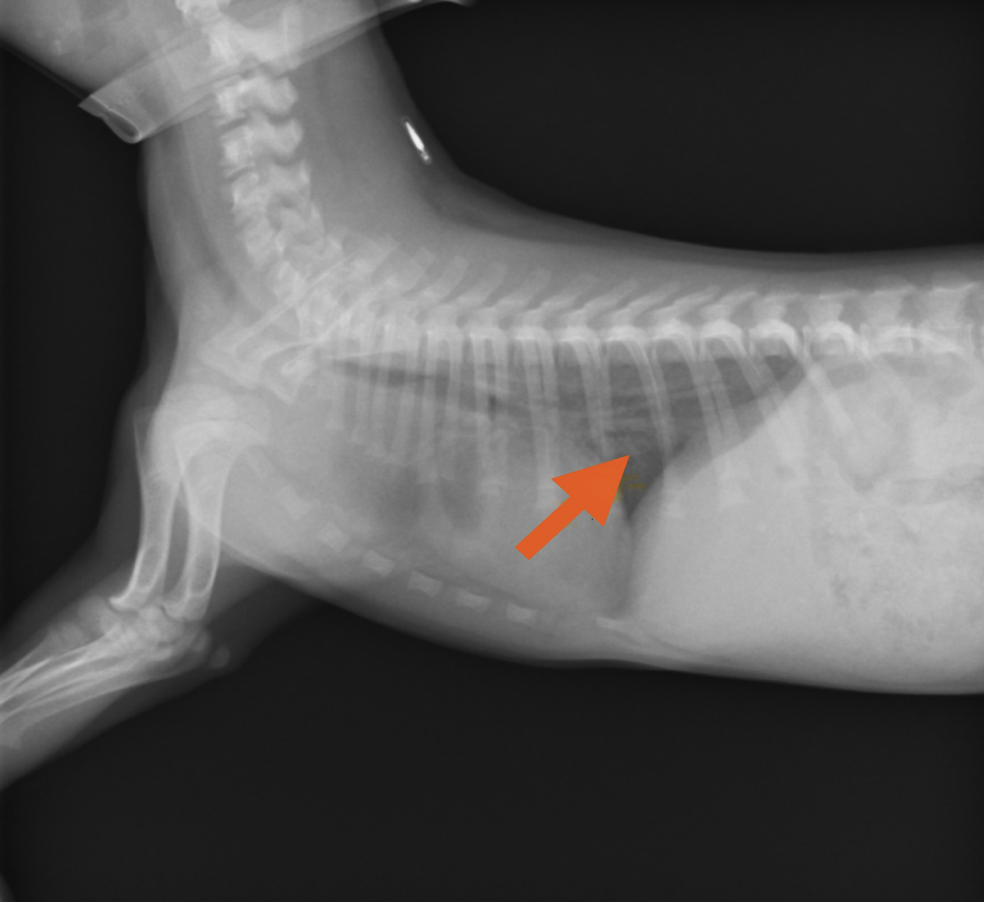

↓本症例のレントゲン写真

赤矢印は、気管支と呼ばれる組織が白くぼやけており、細菌感染やウイルスによって気管支がむくんで炎症を起こしていることを示しています。

さっそく聴診や触診をしましたが、心臓や呼吸の音などに、特に問題はありませんでした。ですが、血液検査では、白血球および「CRP」と呼ばれる炎症を示す値の上昇が見られ、レントゲンでは炎症によって白くぼやけた気管支が見受けられました。

問診および各検査(血液検査、レントゲン画像検査)を総合的に評価した結果、ケンネルコフと診断されました。治療として、抗生剤の処方およびネブライザーの実施を一週間程行いました。その結果、咳の回数も徐々に減っていったため、抗生剤を休薬し、定期的なネブライザーの実施のみ行いました。その後、悪化することなく改善していったため、ネブライザーも終了しましたが、経過に問題が見られないため、治療完了としました。